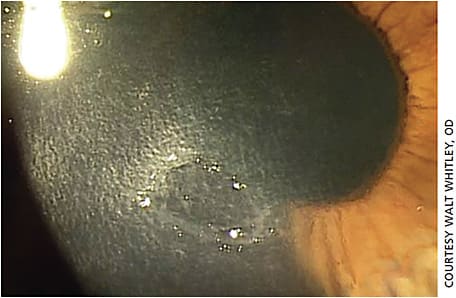

- Stage 1 (mild) NK. Characterized by corneal epithelial irregularity, superficial punctate keratopathy and mild stromal scarring (Figures 1 and 2).

Figure 1. Stage 1 NK. HSV stromal keratitis in a 28-year-old patient who is stable on topical low dose steroid once daily and oral valacyclovir twice daily.

Figure 2. NK Stage 1. A 58-year-old after PKP for keratoconus who underwent a corneal astigmatic keratotomy. Both the PKP and the astigmatic keratotomy led to a surgically induced NK Stage 1. - Stage 2 (moderate) NK. Characterized by a persistent epithelial defect with smooth and rolled edges, Descemet’s membrane folds and stromal swelling and possible anterior chamber inflammatory reaction (Figure 3).